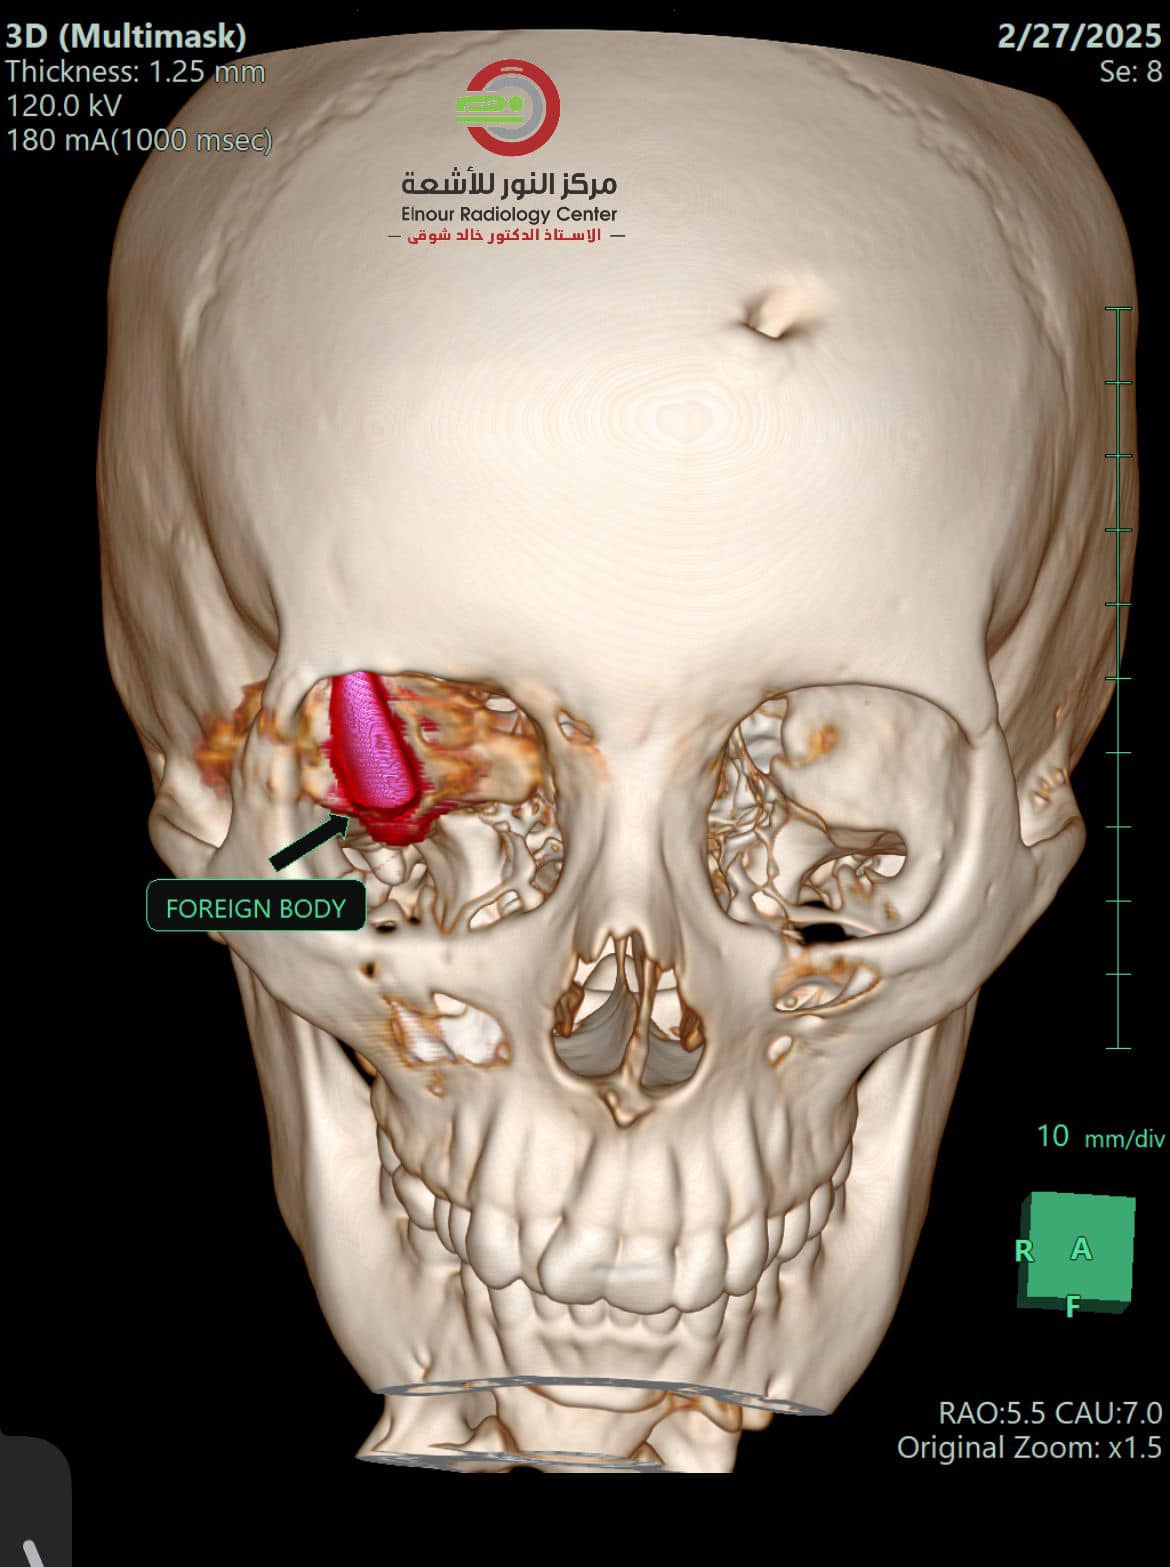

وبحسب المصادر المصرية، تمكن الطبيبان أحمد توفيق ومصطفى عبد الله من إزالة طلق ناري استقر في جمجمة الشابة الفلسطينية، التي خرجت من قطاع غزة لتلقي العلاج في جمهورية مصر العربية.

وكانت الشابة قد أصيبت بطلق ناري اخترق جمجمتها واستقر خلف عينها، إثر استهدافها من طائرة مسيرة من نوع "كواد كابتر"، وذلك خلال نزوحها في منطقة النصيرات.